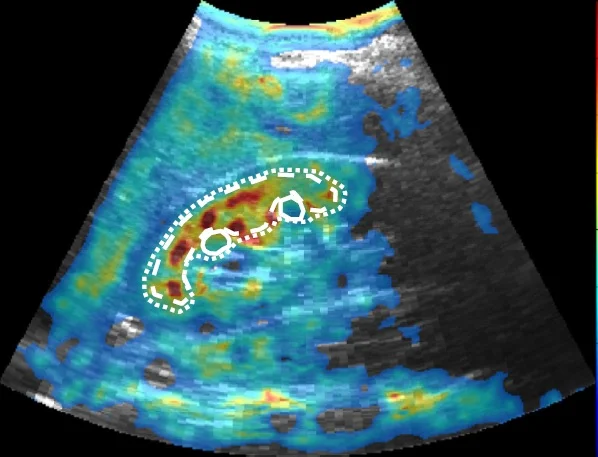

The paediatrician Dr. Christian Hudert and colleagues at Charité Berlin published a study on the diagnostic value of time-harmonic elastography for differentiating stages of fibrosis in paediatric patients who were overweight to extremely obese with non-alcoholic fatty liver disease (NAFLD). Time-harmonic elastography was feasible in all patients (0% failure rate) and may prospectively replace invasive biopsy methods.